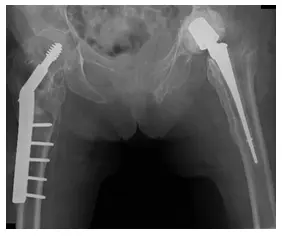

Las radiografías muestran el postoperatorio de una ORIF de cadera derecha y una ORIF de cadera izquierda con colocación de un dispositivo espaciador en la cadera izquierda.

La radiografía muestra osteoporosis con prótesis de cadera izquierda y fijación interna de la cadera derecha, junto con fractura no desplazada del isquion derecho.